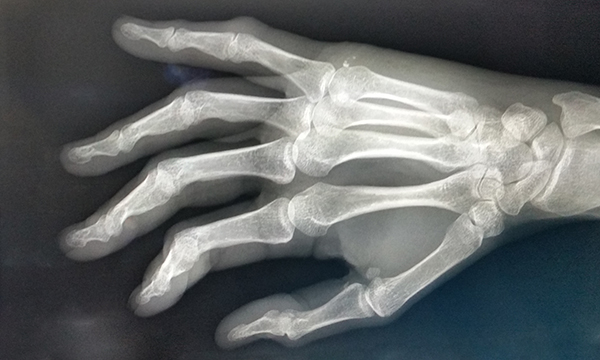

Fight bite injury: emergency department assessment and management

Human bite wounds to the hand are relatively common injuries and are associated with high infection rates. Given the unique anatomy of the hand, the bite mechanism and the organisms found in human saliva, even the smallest wound can result in an aggressive infection. Failure to recognise and treat human bite wounds appropriately, can therefore have negative outcomes for patients. This article outlines the diagnostic features of, and complications associated with, bite wounds and discusses the recommended treatment options.